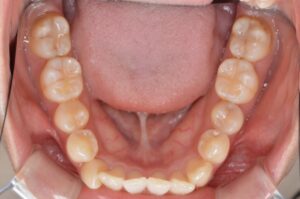

①写真撮影

今の歯並びを色々な角度から撮影します。

せっかくなので矯正前→現在(No.40)で並べてみます。